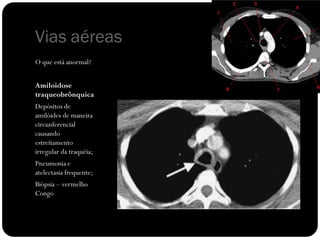

Vias aéreas

O que está anormal?

Amiloidose

traqueobrônquica

Depósitos de

amilóides de maneira

circunferencial

causando

estreitamento

irregular da traquéia;

Pneumonia e

atelectasia frequente;

Biópsia – vermelho

Congo